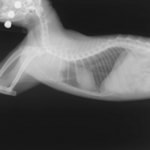

診断:胸部レントゲン検査にて、前縦隔領域に不透過性亢進領域を確認しエコー検査にてFNAを実施。細胞診の結果「低〜中分化型リンパ腫」と診断

前胸部にみられた不透過性領域の退縮が認められます